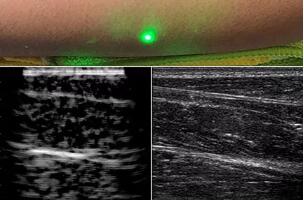

目前,研究人員已經(jīng)與健康的志愿者測(cè)試了他們的系統(tǒng):從半米遠(yuǎn)處掃描了他們的前臂,并將這些結(jié)果與傳統(tǒng)超聲的結(jié)果進(jìn)行了比較。他們能夠觀察到深達(dá)6厘米的組織,并能看到肌肉,脂肪和骨頭,并報(bào)告其結(jié)果可與標(biāo)準(zhǔn)超聲相媲美。